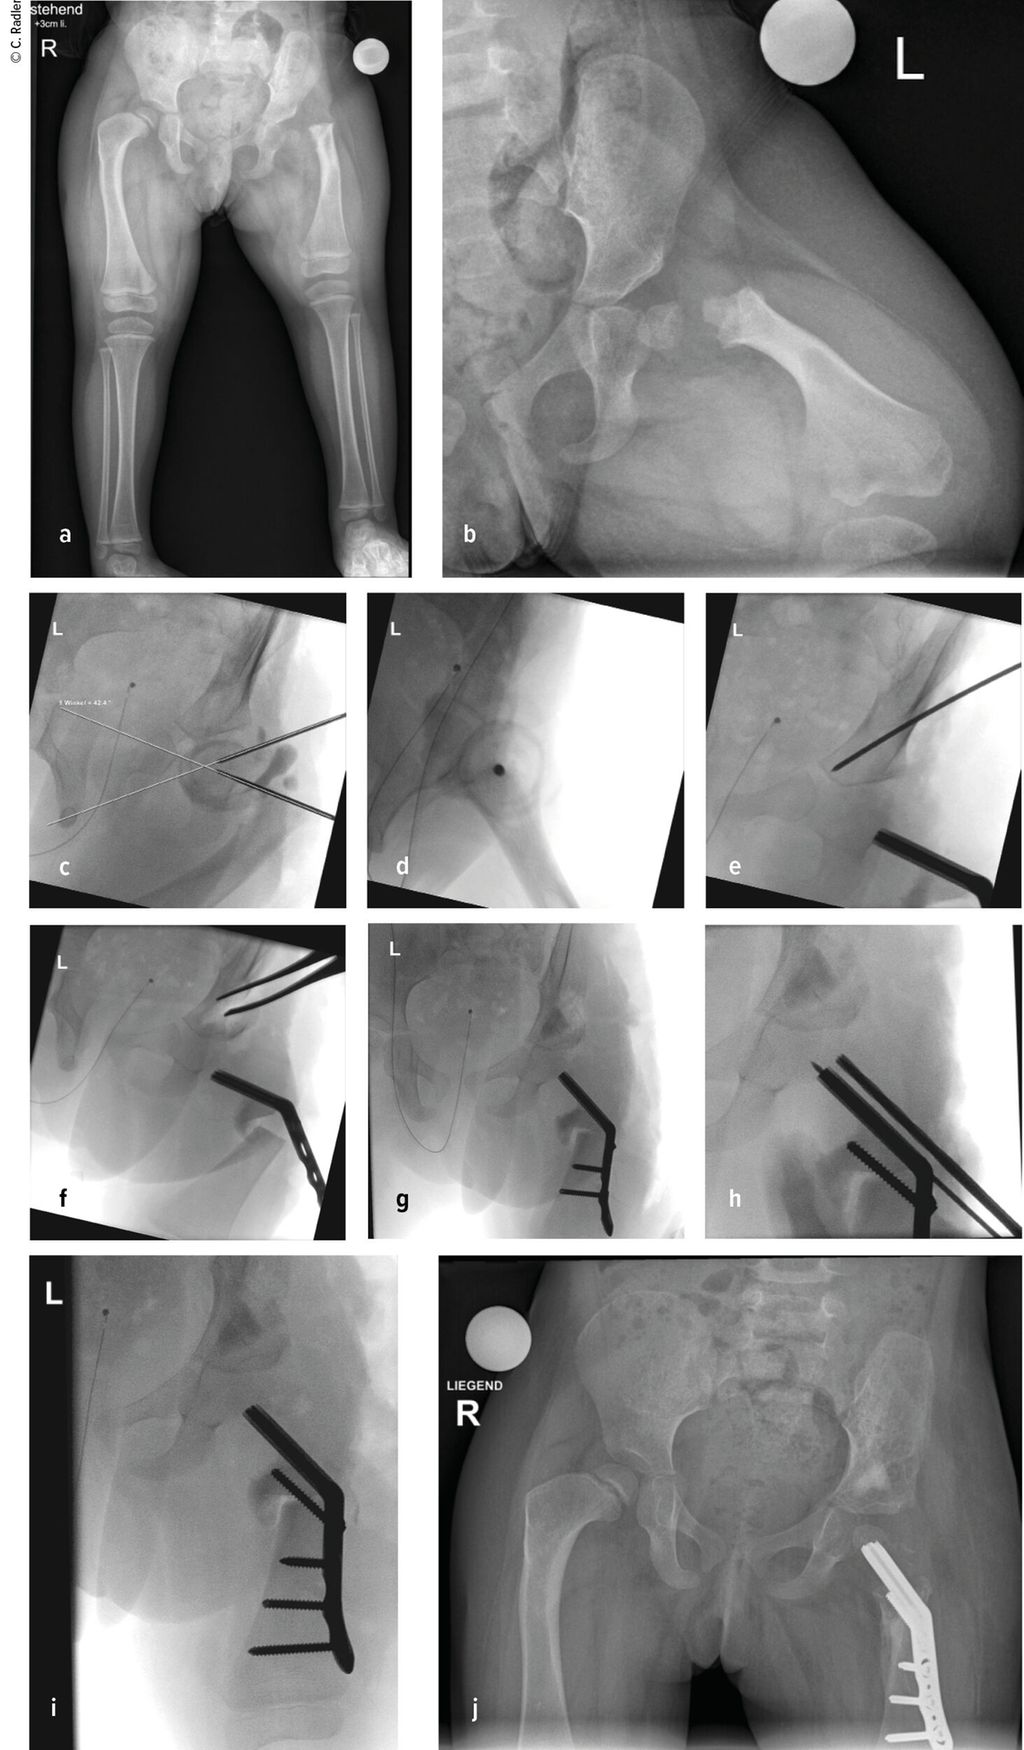

Der kongenitale Femurdefekt ist eine der spannendsten und komplexesten angeborenen Fehlbildungen in der Kinderorthopädie und in der klinischen Präsentation sehr vielgestaltig. Während auf den ersten Blick die Verkürzung des Beins/des Femurs augenscheinlich ist, sind es die assoziierten Veränderungen an Hüfte und Kniegelenk, welche die Therapie herausfordernd machen und vor einer Verlängerung adressiert werden müssen.

Zu den angeborenen Längsdefekten der unteren Extremität zählen neben dem kongenitalen Femurdefekt (CFD) die Fibulahemimelie (FH) und die Tibiaaplasie/-hemimelie. Der Femurdefekt reicht von einer milden Verkürzung des Femurs bis zu seinem fast vollständigen Fehlen, und auch die Fibulahemimelie kann sich von einer milden Verkürzung des Unterschenkels bis zu einer massiven Verkürzung mit schweren Veränderungen am Sprunggelenk präsentieren. Der CFD und die FH kommen fast immer gemeinsam vor, wobei die meisten Fälle eine klare Dominanz der einen oder anderen Pathologie zeigen und die sekundäre Deformität sich oft nur durch minimale Veränderungen an Knochen oder Gelenk präsentiert. Die Tibiaaplasie/-hemimelie ist oft mit Syndromen mit zusätzlichen Fehlbildungen oder Duplikaturen an Hand und Fuß verbunden. Diese Form ist mit einer Inzidenz von 1:1000000 sehr selten.